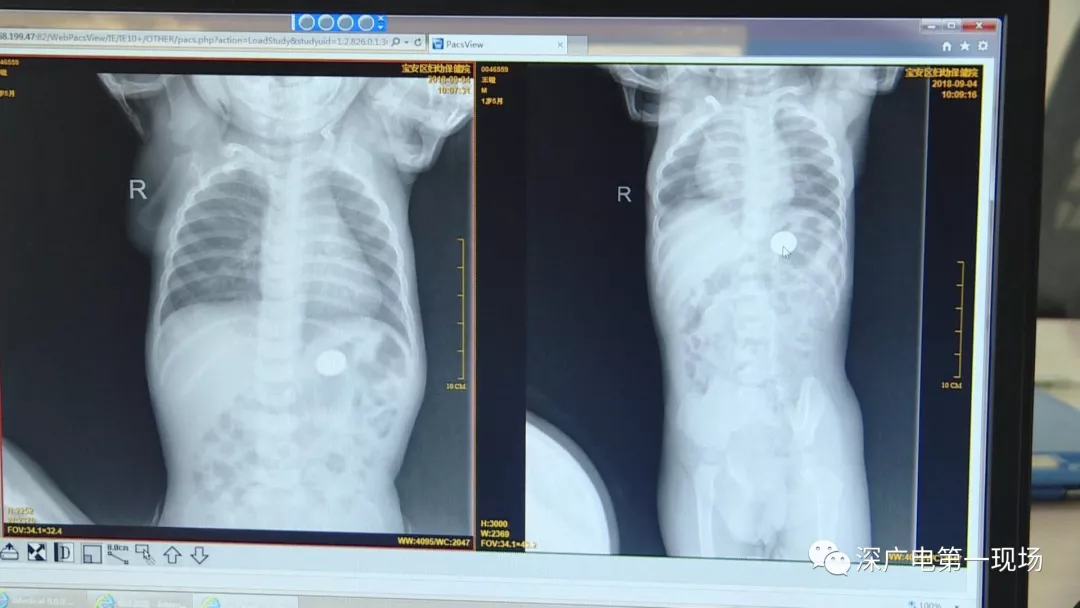

9月4號,一名1歲零5個月的男嬰因在家中摔傷,被父母送到了寶安區(qū)婦幼保健院,醫(yī)生診斷為左側(cè)尺橈骨骨折。在進(jìn)行全麻手術(shù)之前,院方例行對嬰兒進(jìn)行了周身檢查。手術(shù)前,兒外科醫(yī)生趙冠聰在查看患者的胸片時,發(fā)現(xiàn)這名嬰兒的胃部有一枚硬幣大小的暗影。

在與多名醫(yī)生會診之后,醫(yī)生擬定了聯(lián)合手術(shù)方案。

胃部取出一角硬幣

已吞咽半月之久

經(jīng)過兩個小時的時間,兒科醫(yī)生郭景濤為患兒取出了藏在胃底的一角錢硬幣。目前,患兒已經(jīng)痊愈出院。